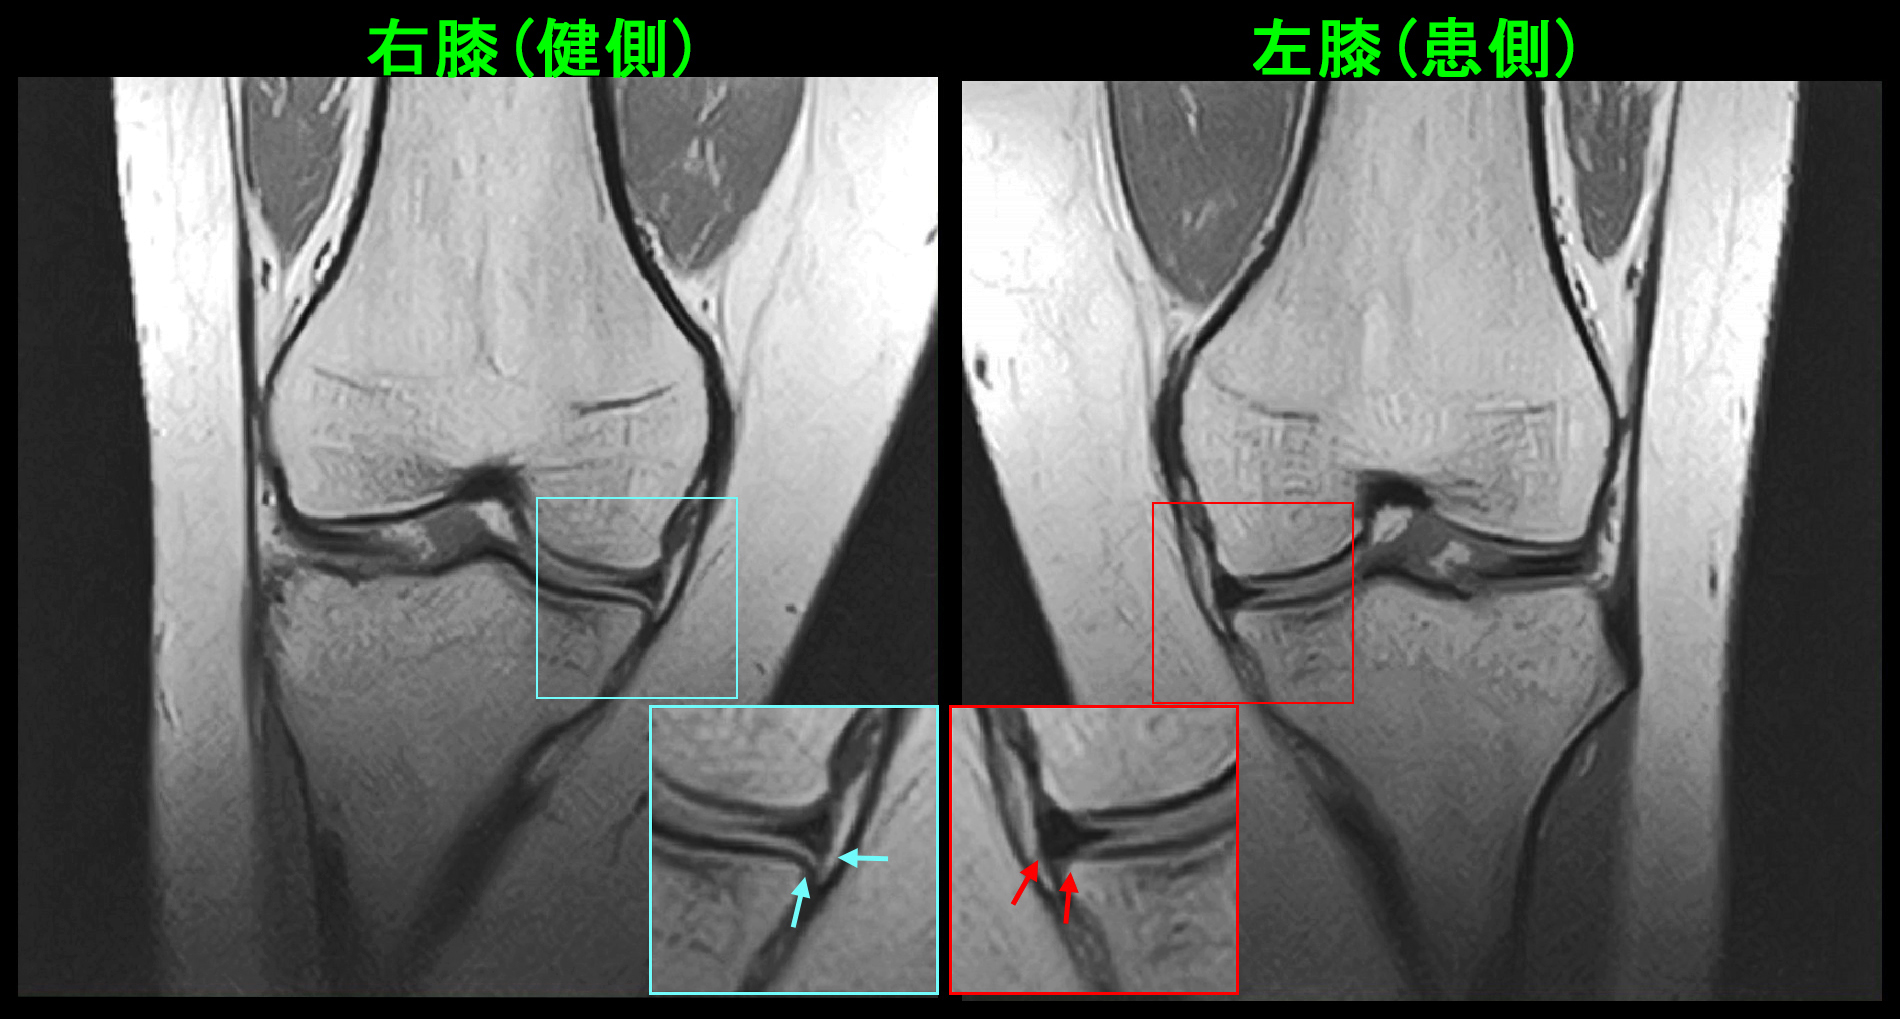

18才女 MR1.jpg

MR所見で左脛骨の骨には異常はありませんでしたが、PDの冠状断(前からみた画像)では左の内側半月板は右に比して膨らんでいる印象です。

18才女 MR2.jpg

同様にPDの冠状断の中央部分では軽度の亜脱臼を認める所見でした。この2つの内側半月板所見は注意深く観察しなければ、見落としても仕方ないような所見です。